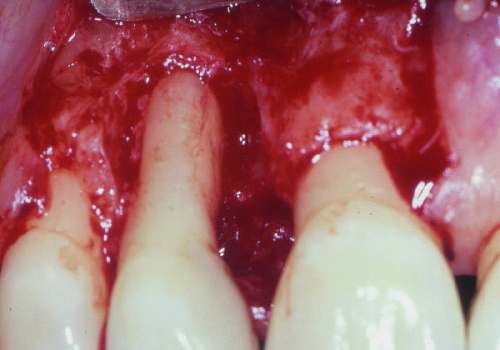

Rezektiv prosedurlar zamanı müəyyən miqdarda yumuşaq toxuma (diş əti), sərt toxuma (sümük) və ya kombinə olunmuş şəkildə (həm sümük, həm də yumuşaq toxuma) rezeksiya həyata keçirilir. Prosedur yerli ağrısızlaşdırma altında aparılır. Əməliyyatdan sonrakı dövrdə fərdi qulluq və gigiyena qaydalarının mötəxəssis tərəfindən izahı və müvafiq instruksiyanın verilməsi olduqca önəmlidir.